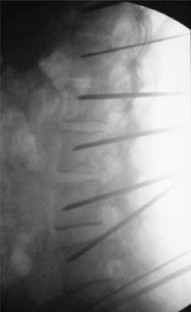

Fig. 2